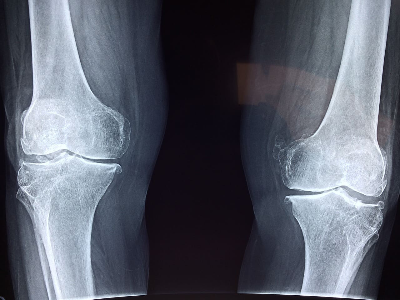

퇴행성 관절염, 연골 손상 등으로 무릎 인공관절 수술을 고민 중이라면 가장 먼저 궁금한 것이 ‘실제 부담금’입니다.

2025년 현재, 무릎 인공관절 수술의 전체 비용은 병원과 수술 범위에 따라 약 250만 원~350만 원 수준입니다.

그러나 건강보험 급여 항목으로 지정되어 있어 본인 부담금은 대략 20% 정도만 부담하면 됩니다.